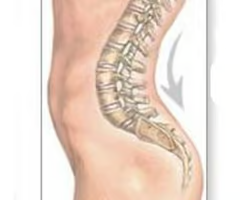

Kyphosis

“Hunchback,” is an exaggerated thoracic curvature.

Lordosis

“Swayback,” is an accentuated lumbar curvature.

Scoliosis

Abnormal lateral curvature, usually in thoracic region.